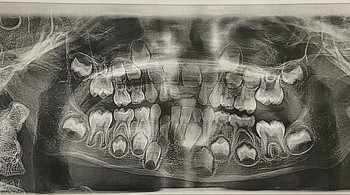

Foto Rontgen Gigi Anak yang Berusia 6 Tahun Foto: Boredpanda